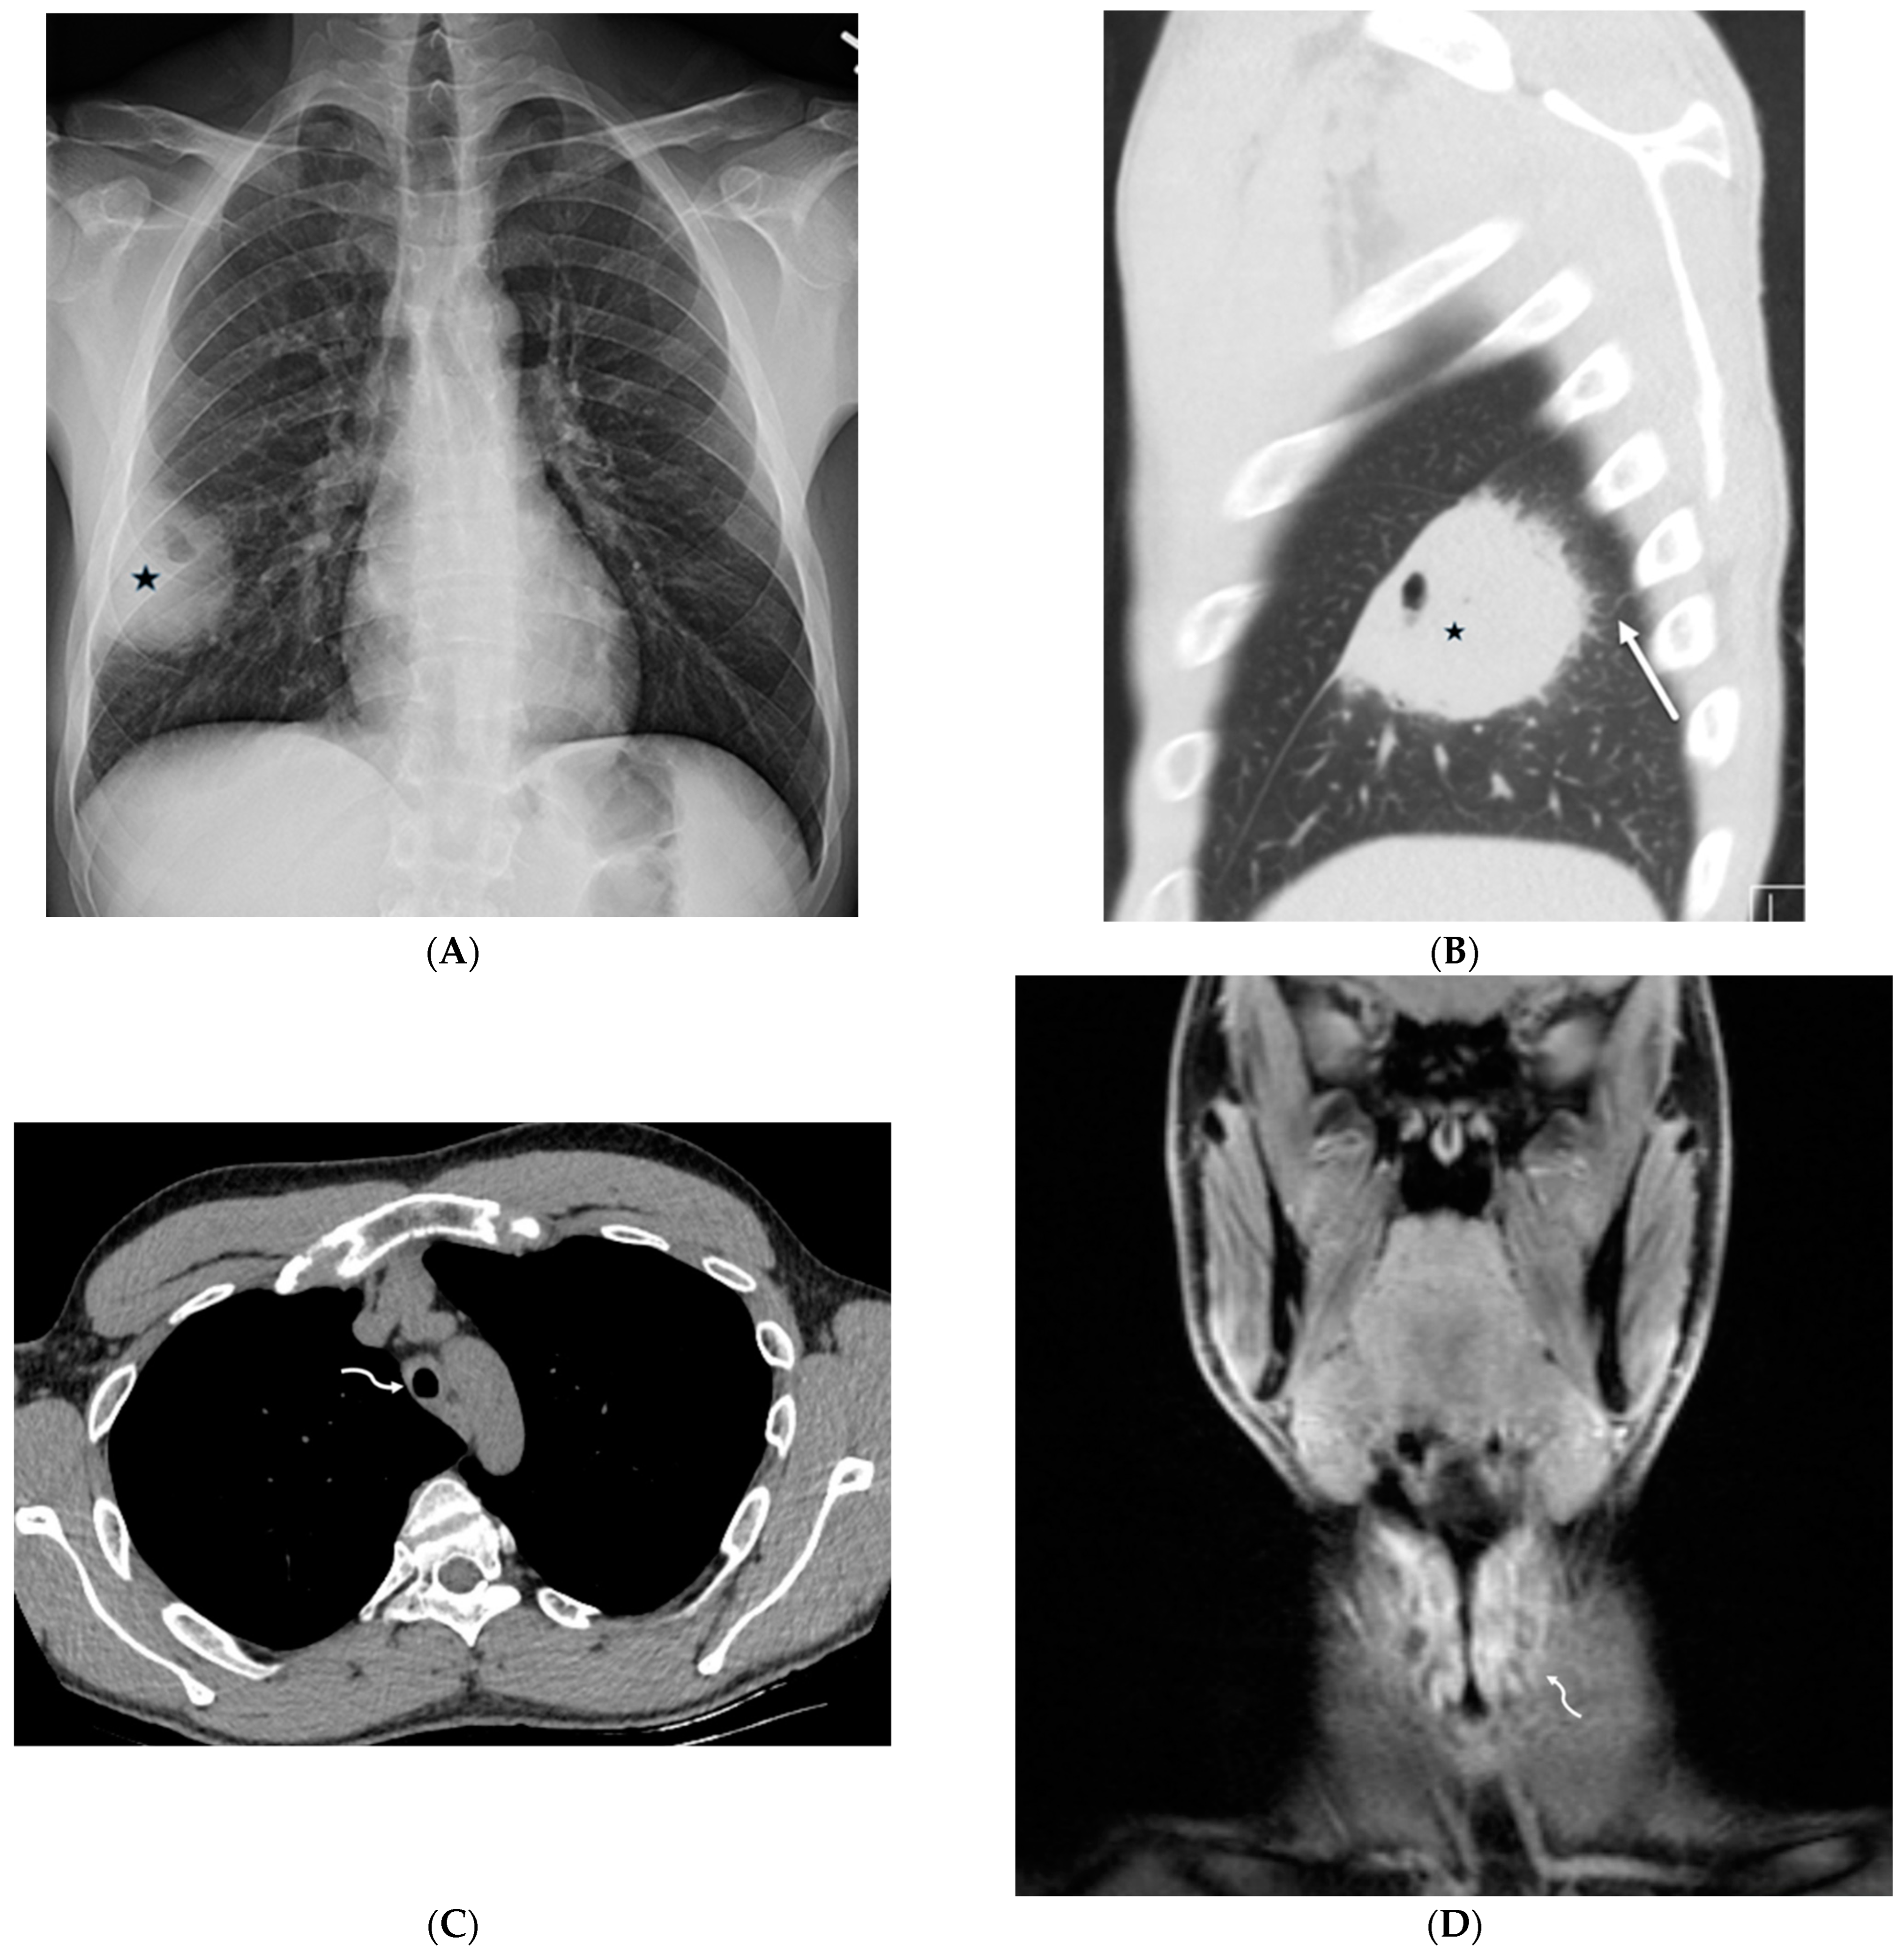

4.7. Pulmonary Vein Stenosis (PVS)

5. Neoplasms

5.1. Invasive Lung Adenocarcinoma

5.2. Kaposi’s Sarcoma

5.3. Lymphoma

7.2. Pulmonary Capillary Hemangiomatosis (PCH) and Pulmonary Veno-Occlusive Disease (PVOD)

7.3. Diffuse Pulmonary Lymphangiomatosis

7.6. Pulmonary Hyalinizing Granuloma (PHG)

7.7. Coatomer Subunit Alpha (COPA) Syndrome